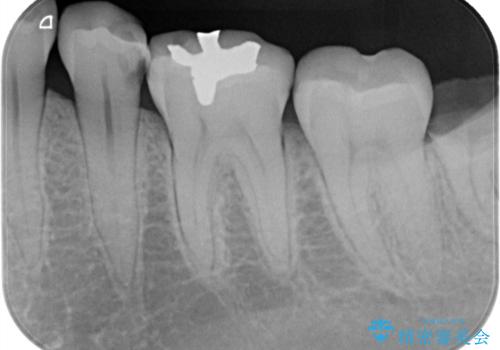

メタル修復物の場合X線を通さない性質があり、レントゲン写真を撮るとメタルの部分が真っ白に写ってしまうため、詰め物の下の虫歯が分かりにくくなってしまうというデメリットがあります。これに対し、今回の即日セラミック修復に使用したMarkⅡという材料は、レントゲン写真からもわかる通り歯の一番外側の部分(エナメル質)と同程度のX線透過性を持ちます。そのため装着後も定期的なメンテナンスにより虫歯の再発を早期に発見できるメリットがあります。